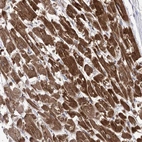

Immunohistochemical staining of human heart muscle shows strong cytoplasmic positivity in myocytes.